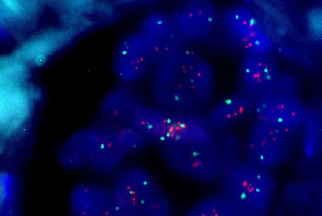

A hibridização “in situ” fluorescente (FISH – Fluorescence In Situ Hybridization) é o mais moderno método de Patologia Molecular para detectar alterações genéticas em associação com a morfologia celular, tais como amplificações, fusões e translocações, que podem ser importantes para o diagnóstico, prognóstico e orientação terapêutica de um grande número de tumores.

É um método de patologia molecular caracterizado pela identificação e localização de ácidos nucléicos alvo (sequências de DNA ou RNA), através da ligação complementar de sondas (sequências de DNA conhecidas, geralmente obtidas comercialmente) marcadas com moléculas fluorescentes (fluorocromos).

A utilização de mais de um fluorocromo no mesmo material permite múltiplas identificações de alterações genéticas através da observação de luz em diversas cores.

A lâmina produzida deve ser observada em microscópio especial para fluorescência, com lâmpada, lentes e filtros específicos para permitir a visualização seletiva do comprimento de onda de cada fluorocromo, além de sistema fotográfico digital especial de altíssima resolução para captura, composição e análise das imagens.